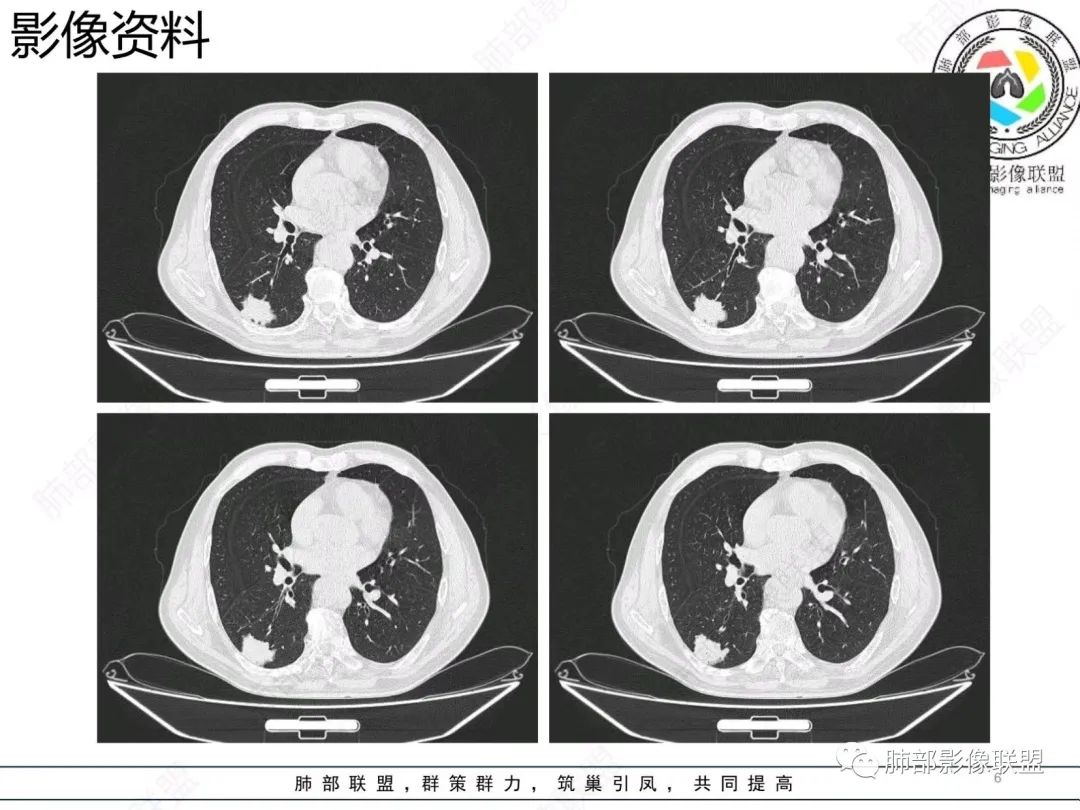

【病例】胸膜下的混合密度结节—良恶之争

老年男性,右肺下叶混合磨玻璃密度结节,可见血管弯征,首先考虑肺腺癌。

右肺下叶背段不规则结节,边界欠清,可见少许晕征,另见胸膜凹陷征及血管弯,考虑腺癌,鉴别隐球菌。

右肺下早不规则结节,周围少许磨玻璃晕,胸膜有牵拉凹陷,虽然部分边界平直,但血管受牵拉弯曲,首先还是考虑肿瘤,腺癌

右肺下叶背段斑片影,边缘平直、局部膨隆,可见磨玻璃密度影,界清,胸膜牵拉,良恶性需要进一步鉴别,倾向隐球,鉴别粘液腺癌。

老年男性,右肺下叶胸膜下结节,边缘见清晰磨玻璃密度影及少许索条,支气管进入后截断,周围血管弯,考虑腺癌,鉴别隐球菌

右肺下叶胸膜下混合密度结节,分叶、毛刺,磨玻璃边界尚清晰,血管集束,支气管进入阻断,考虑腺癌

右肺下叶背段胸膜下肿块,边缘不规则,分叶,毛刺,有磨玻璃,边界清,近肺门侧见血管聚集,支气管进入后闭塞,右肺下叶肺静脉牵拉扭曲。诊断,支持腺癌

老年患者,无呼吸道相关症状,肺部影像学表现:胸膜下占位,有结节融合趋势,内有低密度灶。考虑隐球菌,鉴别腺癌。

胸膜下结节,与胸膜平行,多结节融合,边缘模糊,直边征,考虑炎性肉芽肿,隐球,腺癌

右肺下叶背段实性结节,边缘分叶,较平直,长轴平行胸膜,胸膜增厚,考虑炎性假瘤,隐球菌,鉴别腺癌。

混合性磨玻璃结节,边界清晰,血管打弯,考虑腺癌,鉴别炎性肉芽肿病变。

老年男性,体检发现,无症状,右肺下叶背段肿块影,边缘清楚,无卫星灶,棘状突起,毛刺征,血管集支束,空泡征,考虑恶性肿瘤。

老年男性,体检发现。右肺下叶混合磨玻璃结节,渗漏征,短毛刺,血管集支束,空泡,考虑腺癌。

老年男性右肺下叶靠近胸膜一不规则混合密度影,周围有渗出,内见支气管扩张,考虑炎性病变隐球鉴别腺癌

老年男性 右肺下叶胸膜下见一团状实性病灶+边缘磨玻璃,边缘形态不规则,,局部有平直,长轴平行于胸膜面,整体收缩力偏弱,邻近胸膜面轻度增厚,纵隔窗显示病灶内可见支气管充气,考虑炎性肉芽肿,隐球菌可能,鉴别黏液腺癌。

右肺下叶实行病灶,边缘部分有边界清晰的磨玻璃影,实变明显层面,可见平直。考虑腺癌

右下肺近胸膜病变,周围可见磨玻璃影,界限无法判断清楚?模糊?。考虑右下肺占位:真菌感染?腺癌?淋巴瘤?

右肺下叶胸膜下结节,边界清楚毛玻璃,有分叶、毛刺、血管集束及胸膜增厚,考虑肉芽肿性病变,鉴别于腺癌

右肺下叶实性病灶,局部平直,考虑炎性病变,隐球菌可能

胸膜下结节,长轴与胸膜平行,边缘模糊,直边征胸膜凹陷牵拉不明显,考虑炎性肉芽肿,隐?鉴别腺癌。

右肺下叶后基底段胸膜下斑块影,边缘清楚,有平直和膨隆特点,周围清楚GGO,较模糊(似清非清,邻近见多发纯GGO结节,以肺腺泡分布,主体病灶与胸膜平行,收缩力弱,边缘见支气管充气征,首诊断炎性肉芽肿,抗炎治疗和查下隐球荚膜抗原两方面进行,另取旧片对比,与粘液腺Ca鉴别,最后经皮肺穿刺病理诊断!

上面这些征象存在炎性病变可能,我先考虑炎性病变——隐球,这样的血管弯在肺隐球菌病里也出现过。腺癌尤其是粘液腺癌也不敢排除。建议完善血隐球菌荚膜抗原、经皮肺穿刺活检等检查。